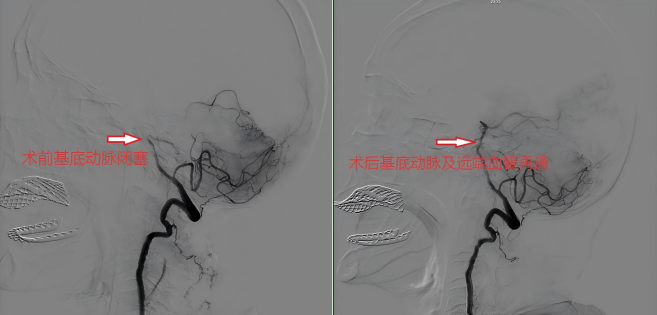

据悉,患者陈婆婆因突发左侧肢体完全瘫痪1小时被家属送至大竹县人民医院急诊科,急诊科立即启动“脑卒中绿色通道”,急诊抽血,急诊头颅CT提示颅内未见出血及梗死灶,急诊科以“脑梗死”收入神经内科。神经内科李朝晖主任团队立即详细询问患者病史并进行仔细的专科查体后诊断为脑梗死。高龄+脑梗死这一情况,对神经内科医疗团队来说无疑是一个不小的挑战,内科保守治疗很有可能效果不佳导致终身残疾甚至进一步加重死亡,静脉溶栓又担心会出现出血导致更严重的后果,于是经过团队积极讨论分析,神经内科医疗团队为患者提出了神经介入的治疗方案。在征求患者子女同意后,迅速为患者进行了“主动脉弓造影术+全脑血管造影术+基底动脉栓塞血栓抽吸术”,经过40多分钟的努力,成功取出血栓,开通患者闭塞血管。此次手术取得良好治疗效果,术后第二天患者便可下床行走,一个星期后顺利出院,患者和患者子女多次诚挚感谢神经内科的救命之恩。